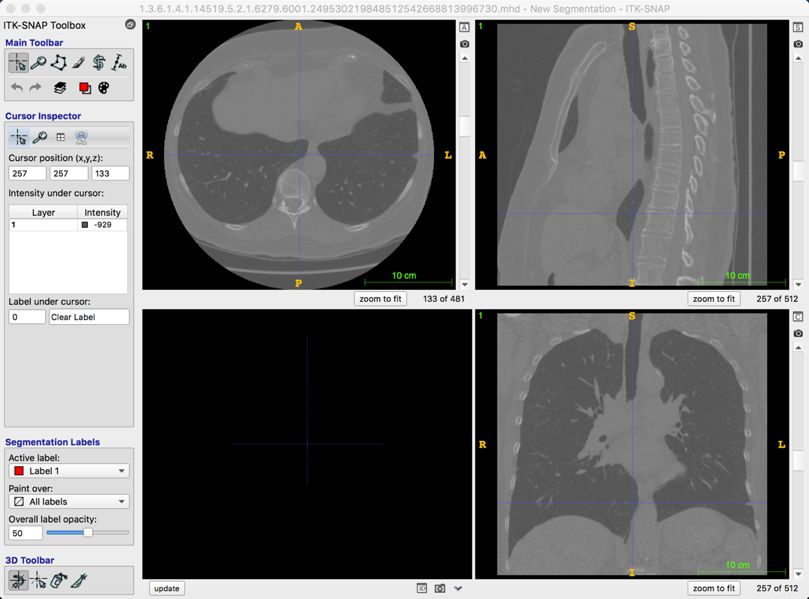

医疗影像分析

2017 年 7 月,国际权威肺结节检测大赛 LUNA16 要求选手对 888 份肺部 CT 样本进行分析,寻找其中的肺结节。样本共包含 1186 个肺结节,75% 以上为小于 10mm 的小结节。最终,阿里云 ET 在 7 个不同误报率下发现的肺结节平均召回率达到 89.7%。(召回率指在样本数据中成功发现的结节占比,下图显示了 ET 在不同误报次数下的召回率情况。)

(FROC曲线)

其背后的技术由阿里巴巴 iDST视觉计算团队完成,负责人华先胜介绍,与常用的两阶段检测方法不同,他们创新性地使用了单阶段方法,全程无须人工干预。机器全自动读取病人的 CT 序列,直接输出检测到的肺结节。在模型结构设计上,ET 针对 CT 切片的特性,采用多通道、异构三维卷积融合算法、有效地利用多异构模型的互补性来处理和检测在不同形态上的肺结节 CT 序列,提高了对不同尺度肺结节的敏感性;同时使用了带有反卷积结构的网络和多任务学习的训练策略,提高了检测的准确度。比赛中,团队克服了一系列挑战:如结节模态复杂问题,早期的结节小(小于10mm),传统的机器学习和用于自然图像的深度学习网络通常难以凑效。

肝结节的准确测量可以辅助医生做出决策和治疗方案。但肝结节形态多样,即使是同一个病人,结节的大小、形状都不一样,从而导致结节间灰度分布差异大、或与周围组织灰度相似,甚至没有清晰的边界。

阿里则通过对 CT 图像层间信息和层内信息融合的网络结构分析,解决肝结节类别多样性的问题。采用基于原子卷积的空间金字塔池化(Atrous Spatial Pyramid Pooling)、亚像素卷积(Sub Pixel Convolution)及多特征融合等技术。华先胜表示,目前团队研究范围已经覆盖肺、肝、骨、心脏、脑等部位的疾病,涉及影像分析、自然语言处理、设备信号处理等相关技术,部分技术已经落地到实际的医疗诊断中。